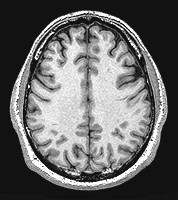

Your cerebrum is actually divided into two halves, called the right and left hemispheres. Each half of the cerebrum is responsible for different tasks. Information is shared between the halves by way of the corpus callosum.

The two hemispheres of the brain, as seen in cross section from above, in a photo taken by an MRI machine.